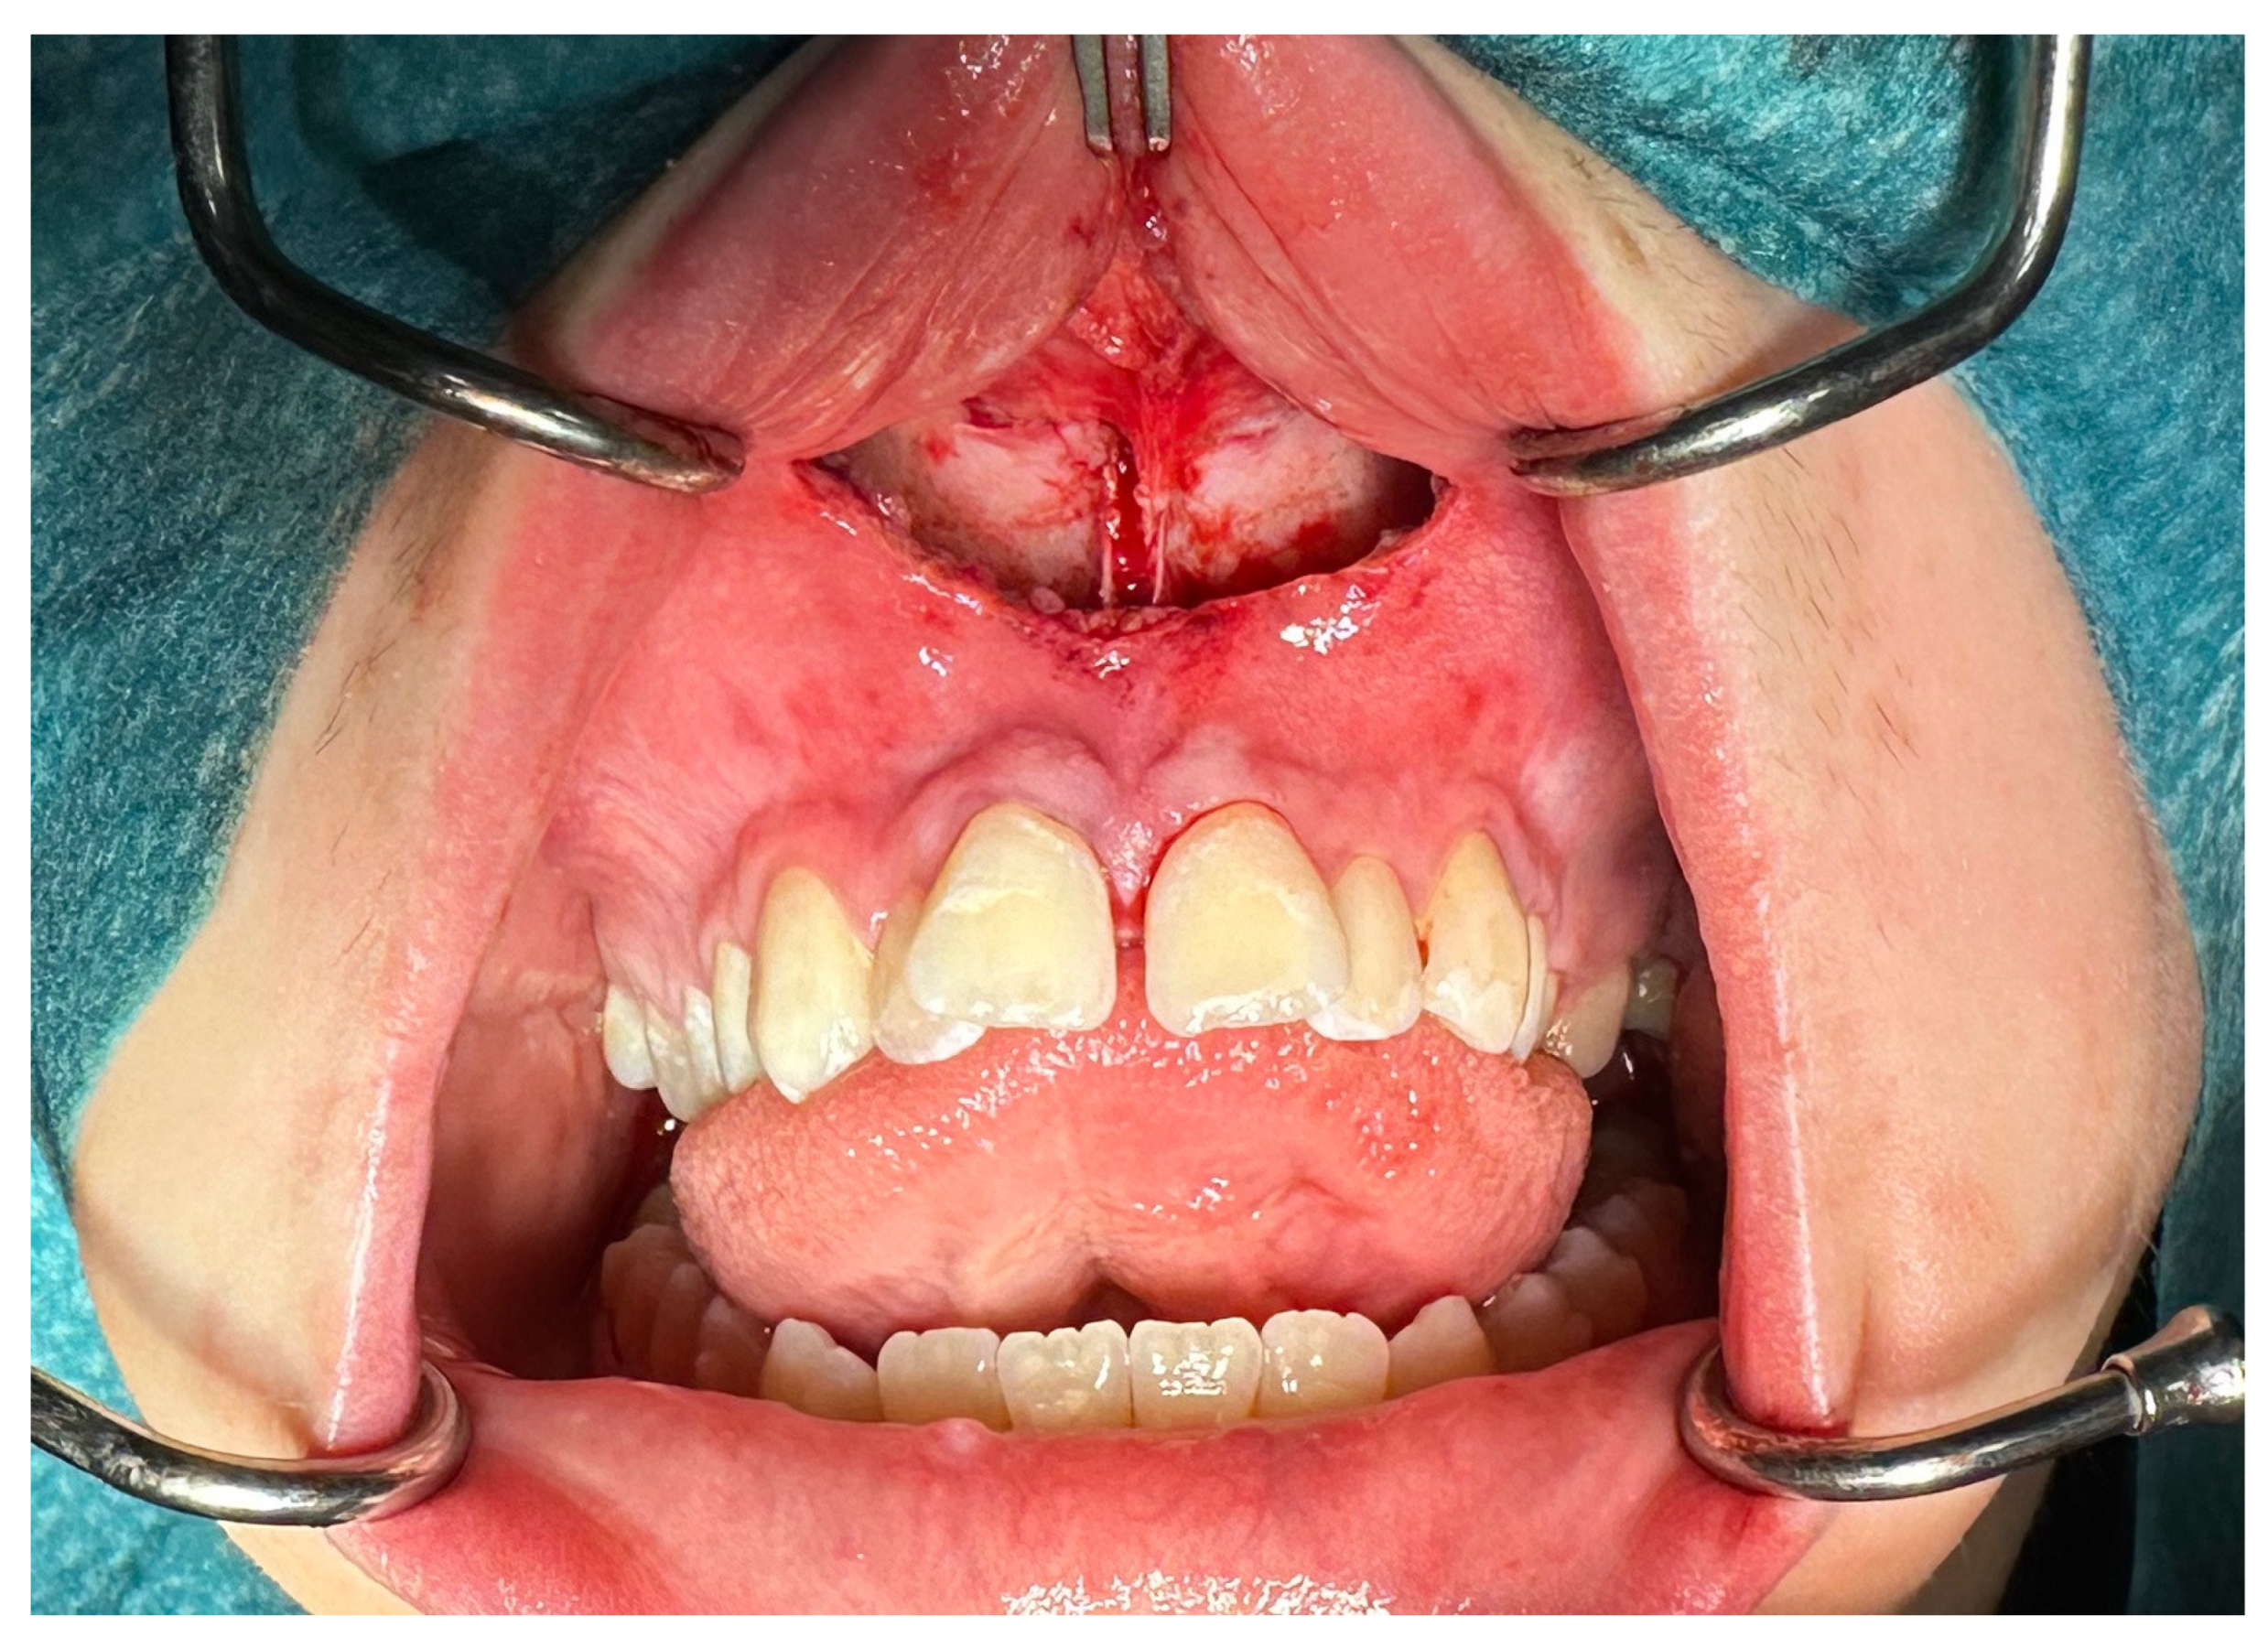

| No possibility of distraction—1 case | Maxillary incisor root resorption—2 cases |

| Palatal mucosal necrosis—2 cases | Bone loss/lack of adhesion in the distraction gap—5 cases |

| Perforation of the maxillary alveolar process caused by the distractor—1 case | Maxillary incisor necrosis—2 cases |

| Asymmetric distraction—5 cases | |

| 9 cases (4.86%) | 9 cases (4.86%) |